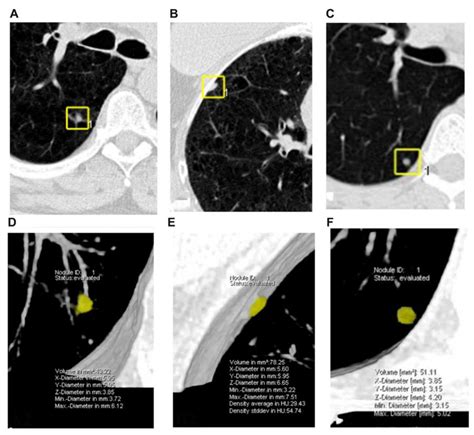

• CT Scan: Computed tomography (CT) scans offer high-resolution images and are more sensitive in detecting smaller nodules. They are often used for follow-up and monitoring.